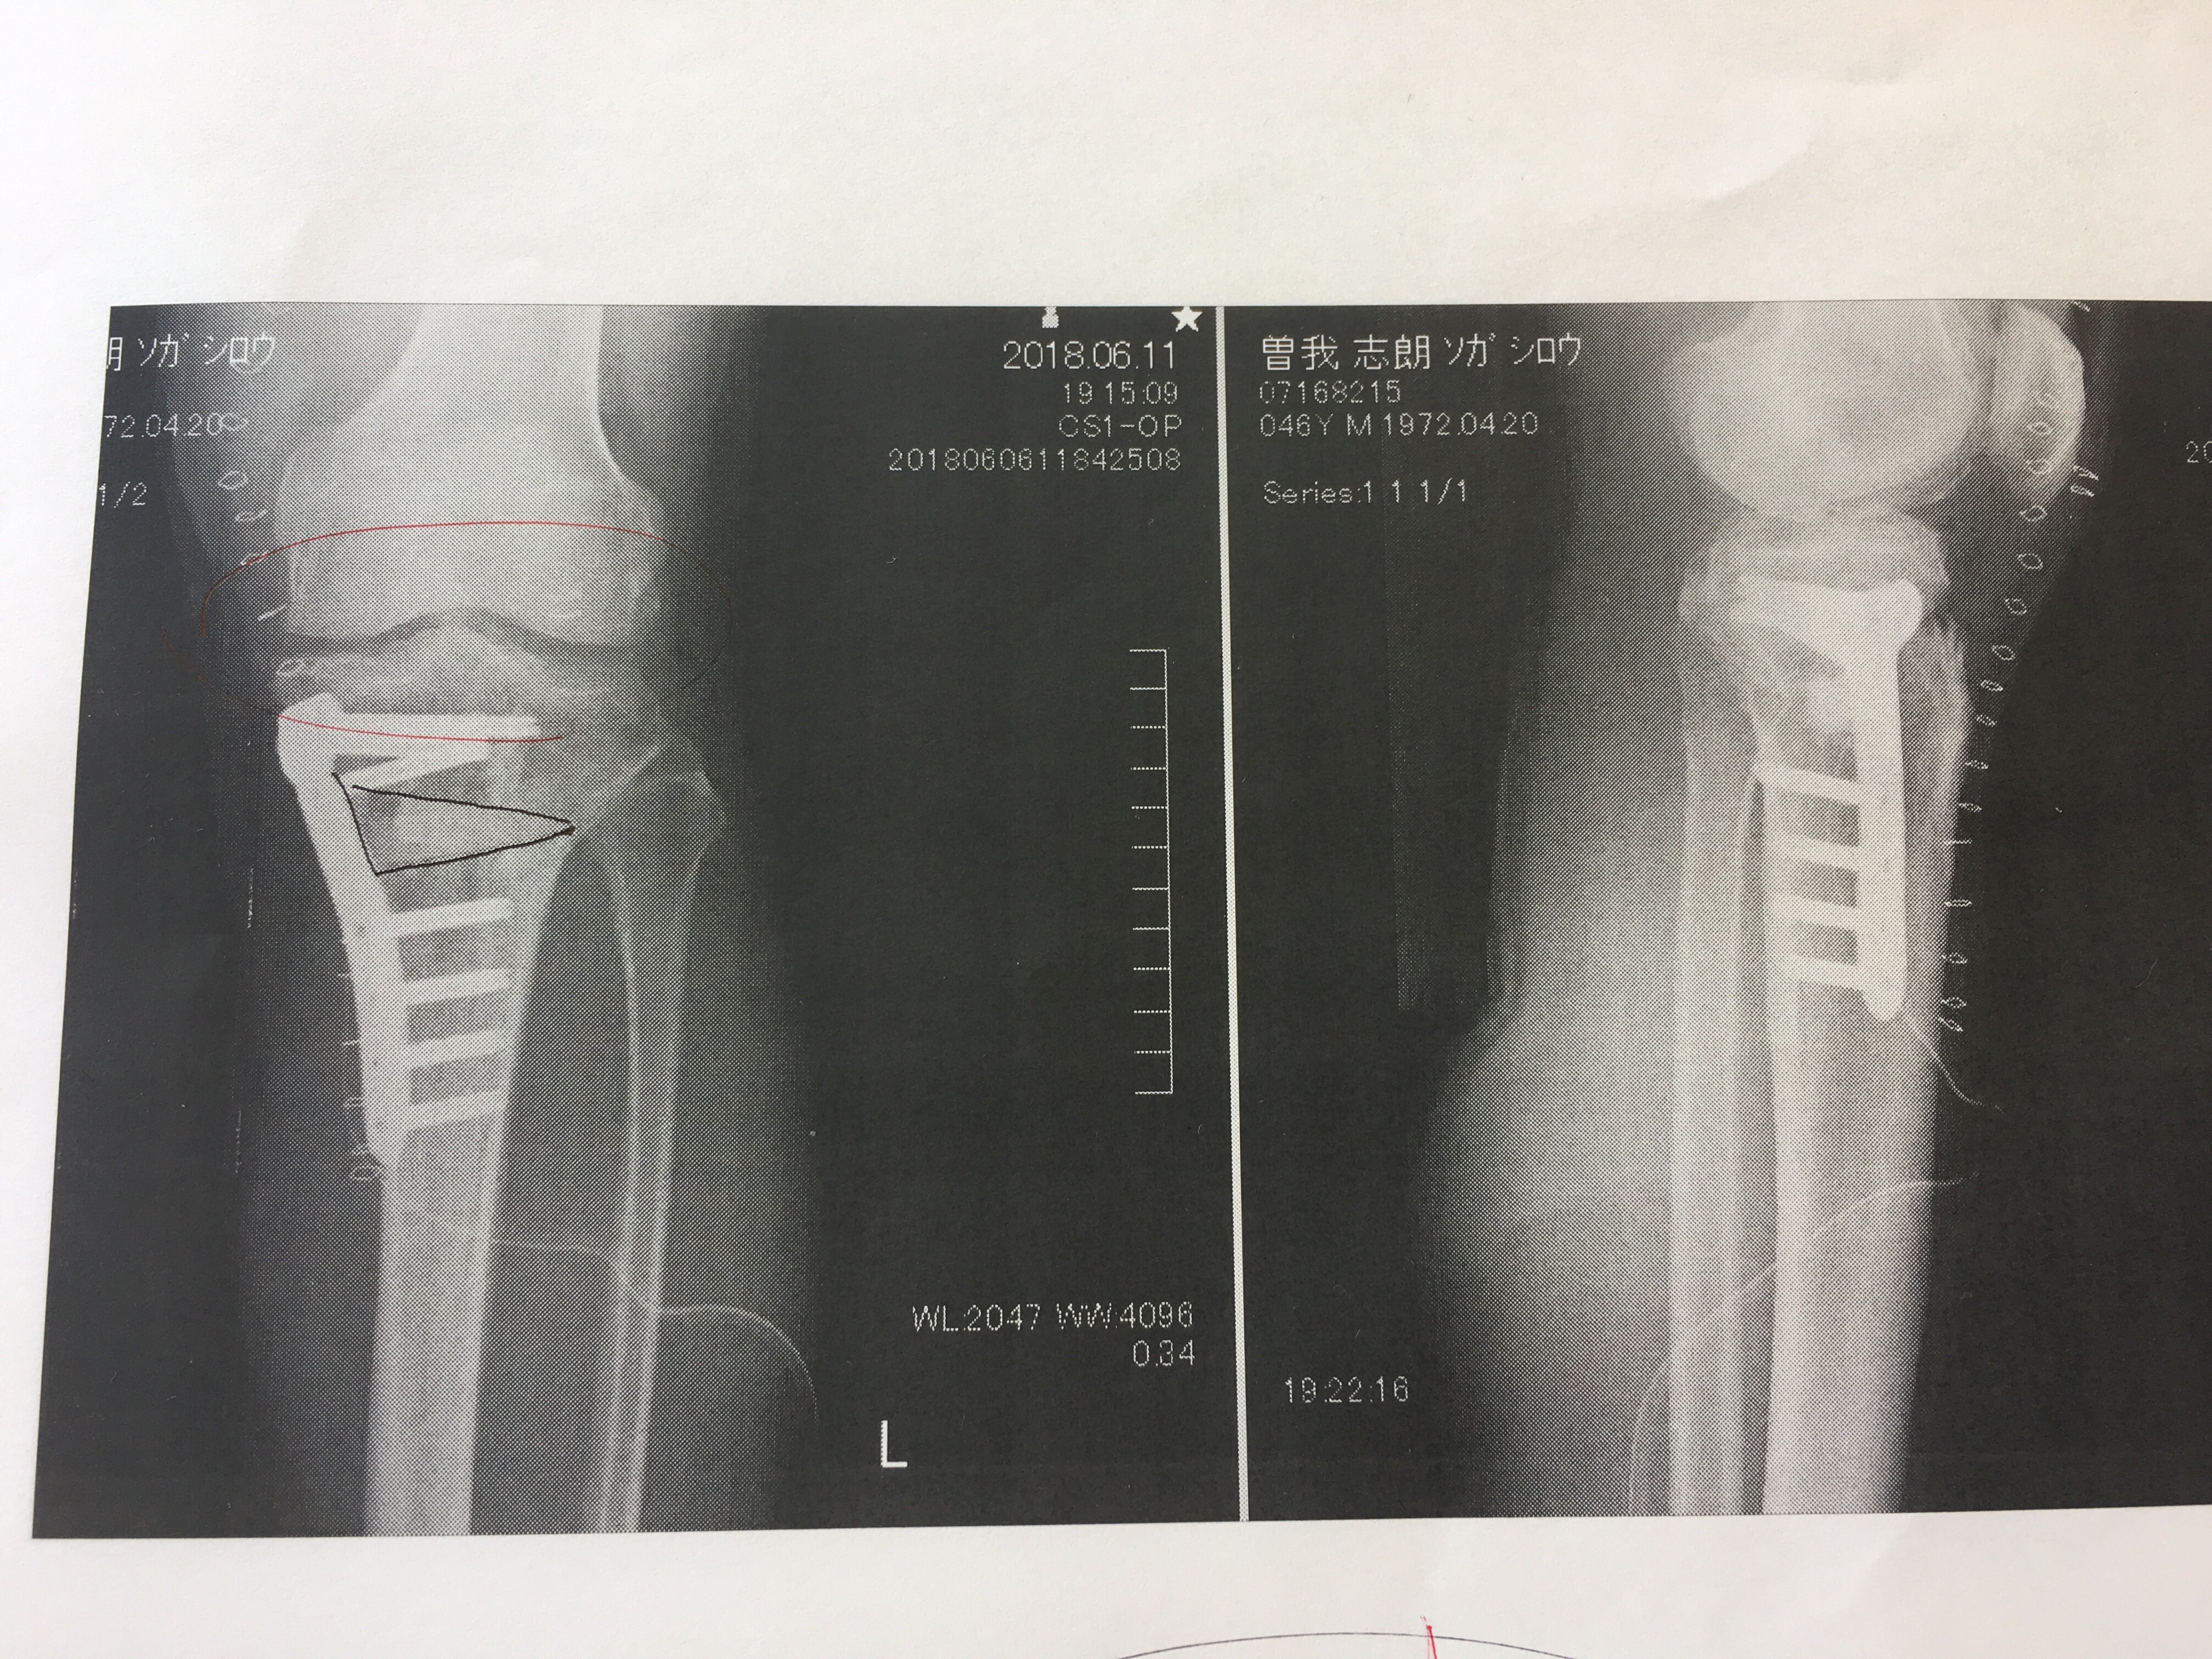

ちなみに、長年膝を無意識に庇っていたため、左足に関してはO脚になっていたらしいんですが、それも今回治そうということで、骨切してから人工骨を埋め込み、それをプレートで固定するという手術もしているんだそうです。

これで、ちょうど真ん中に過重がかかるようになったんだそうで。

ちなみに、人工骨はそのまま放置しておくと、自分の骨と一体化するんだそうです。

最終的には、そのプレートを1年後に除去し、同時にゆるんでいる靭帯を再建して、今回の手術は完了だとのこと。